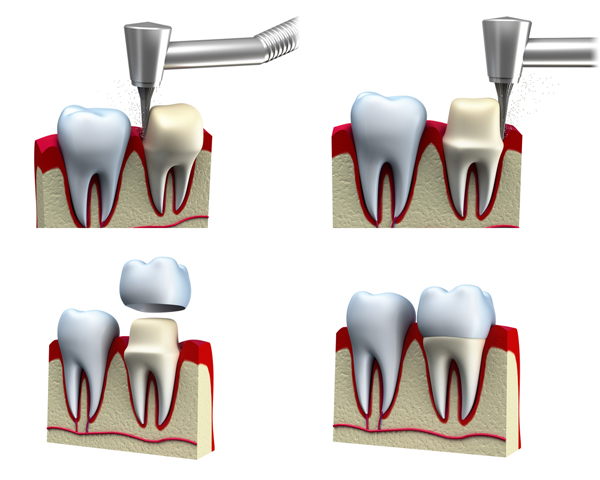

Kroon- en brugwerk

Door kronen te plaatsen kunnen wij de kleur en de vorm van uw tanden verfraaien. Met bruggen kunnen wij tanden en kiezen die u mist vervangen.

Wij maken dan gebruik van de wortels van de tanden en kiezen die u nog heeft. Op de huidige tand of kies maken wij kronen die onzichtbaar aan elkaar verbonden zijn met een of meer tussenliggende tanden of kiezen.

Er wordt dus een tussenliggende ruimte overspannen, de “brug”. Het uiterlijk van uw gebit wordt door de behandeling hersteld of verbeterd met een vastzittende onzichtbare constructie. Soms wordt gekozen voor een implantaat in plaats van een brug. De tandarts kan u hierover adviseren.